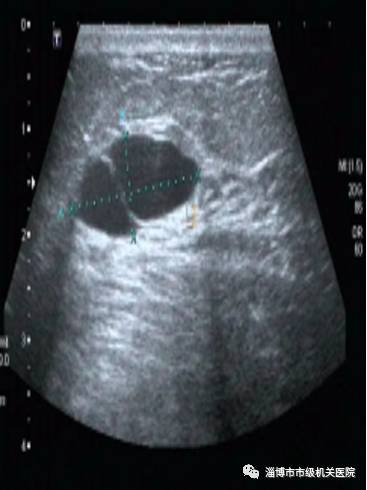

一、超声擅长辨别肿块

超声的优势:

1. 乳腺超声没有放射性,可以根据需要反复检查。

2. 超声能清楚分辨层次,鉴别囊性与实性肿块的准确率可达100%,能大致判断肿瘤的良恶性。

3. 超声科引导穿刺活检。

4. 超声还可以了解腋窝和锁骨上淋巴结有无转移。

超声的劣势:超声对很多细微钙化灶难以分辨清楚。